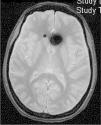

TC craneal: suele ser normal, aunque se han descrito senos venosos ingurgitados, ventrículos pequeños, colecciones de fluidos subdurales (fig. 4), obliteración de la cisterna prepontina e imágenes de pseudohemorragia subaracnoidea (hiperdensidad del tentorio y en la cisura de Silvio)49.

RM cerebral con gadolinio (Gd+) iv: es la exploración de neuroimagen de elección para confirmar la sospecha clínica de HIE, siendo diagnóstica en un 80%49. Se han comunicado sus resultados en más de 2.000 pacientes con HIE y los signos informados aparecen en la tabla 1048,49. La captación paquimeníngea de Gd+, difusa y homogénea, es el signo radiológico más frecuente (fig. 2). No obstante, la valoración de estos signos radiológicos requiere entrenamiento para evitar arbitrariedad. Por ello, se han desarrollados escalas como la de Bern (tabla 11)59,60. Los hallazgos en la RM dependen del tiempo de evolución de la enfermedad61.

Tabla 10.Signos radiológicos de HIE en RM craneal

■ Captación paquimeníngea difusa de Gd+ (73-80%) que en la mayoría de los casos se puede apreciar también en secuencia FLAIR sin Gd+. (fig. 2) ■ Colecciones de fluidos extra-axiales (35-50%), siendo el 60% higromas y el 40% hematomas (fig. 4) ■ Descenso cerebral desproporcionado al tamaño de las colecciones de fluidos (43%). Pueden aparecer los siguientes signos: ■ Colapso ventricular ■ Angulación del quiasma óptico ■ Aplanamiento de la protuberancia contra el clivus con obliteración de la cisterna pontina, ■ Descenso del cuerpo calloso ■ Descenso amigdalar ■ Ingurgitación venosa (57%) ■ Aumento del tamaño hipofisario (38%) ■ Pneumoencéfalo intraventricular (fig. 5) en casos de HIE yatrogénico ■ Disminución del diámetro y grosor del nervio óptico en secuencia coronal T2, también detectable con ecografía transorbitaria Tabla 11.Escala de Bern. Signos de HIE en RM craneal